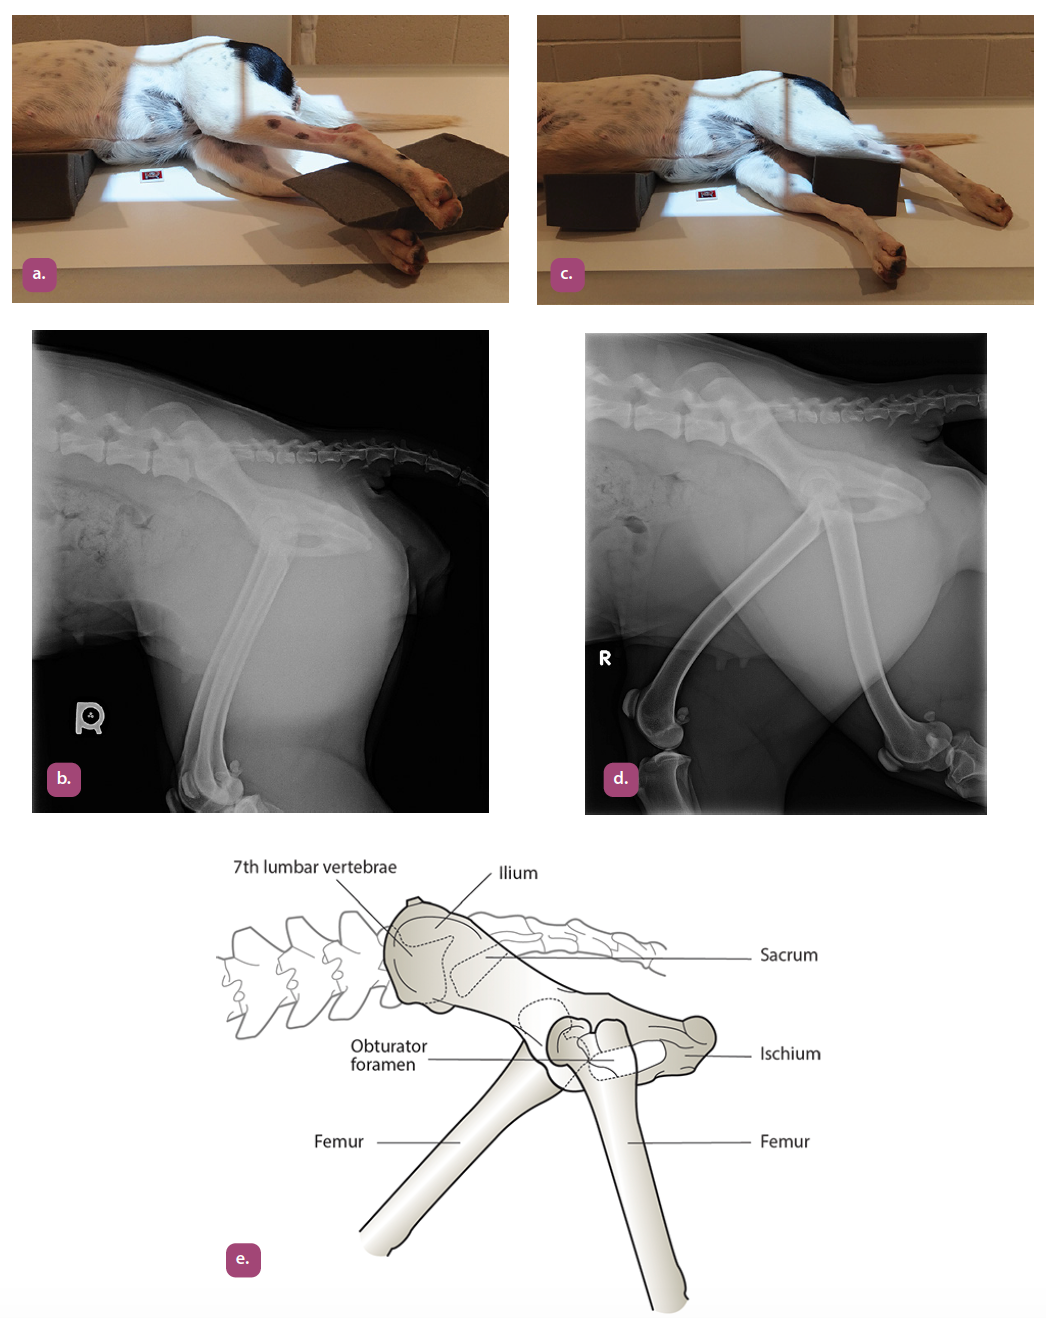

lateral projection of the pelvis

ventrodorsal extended hip projection

ventrodorsal frog leg projection